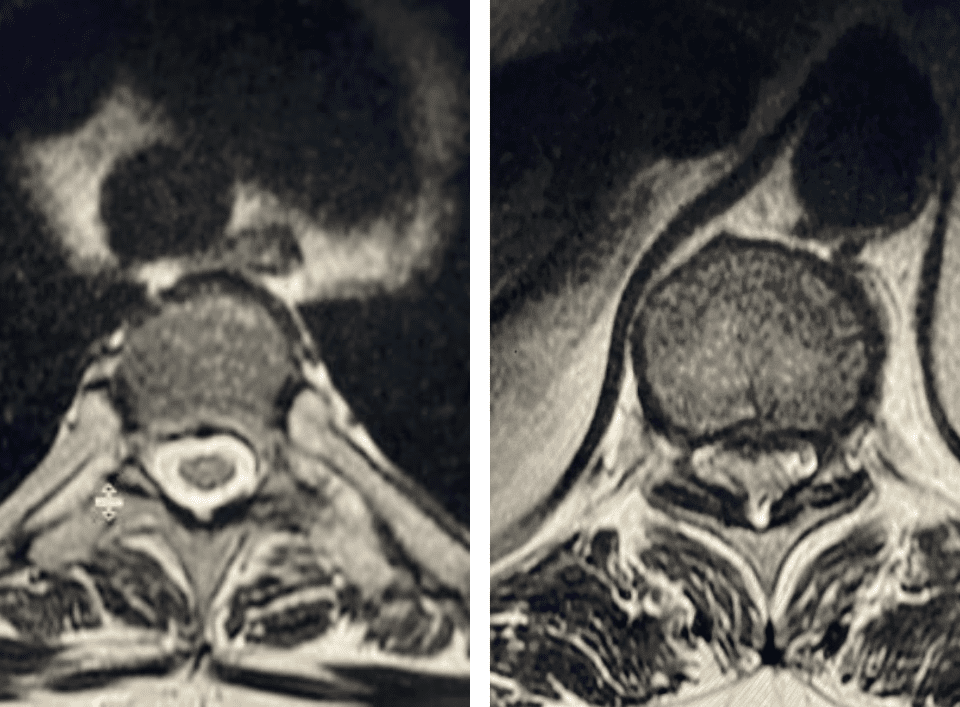

Thoracic stenosis is far less common than lumbar stenosis. Whereas the symptoms of lumbar stenosis are usually well-defined, thoracic stenosis can act like a great mimicker, […]

Nervous tissue is soft. The thecal sac is surrounded by a rigid bony ring which forms the spinal canal. Any mass that fills the very small […]